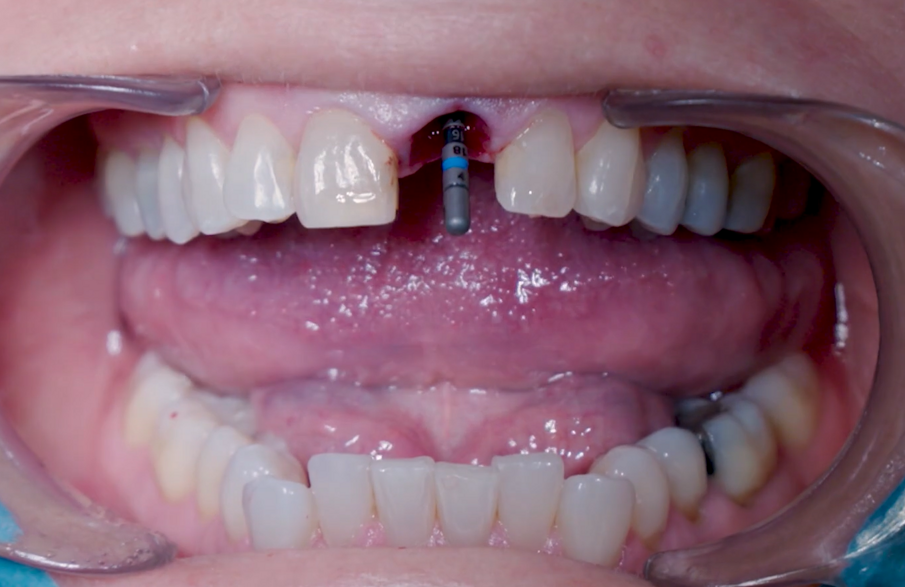

Una paziente di 53 anni si è presentata in studio con un incisivo sinistro fratturato a cui era stata più volte cementata una corona di ceramica (Figg. 1, 2). L’anamnesi e gli esami hanno evidenziato una buona salute sistemica e orale, un’occlusione ben equilibrata e nessuna abitudine al fumo. La tomografia cone beam (CBCT) e la radiografia periapicale hanno mostrato un riassorbimento radicolare esterno con inserimento nell’osso alveolare molto scarso, insufficiente per un adeguato posizionamento di un comune perno endocanalare (Figg. 3, 4). Considerando che il dente fratturato si trovava nella zona estetica, il paziente richiese un restauro nel modo più sicuro e più veloce possibile.

Fig. 1_Situazione iniziale, visione extra-orale.

Fig. 2_Situazione iniziale, visione intra-orale.